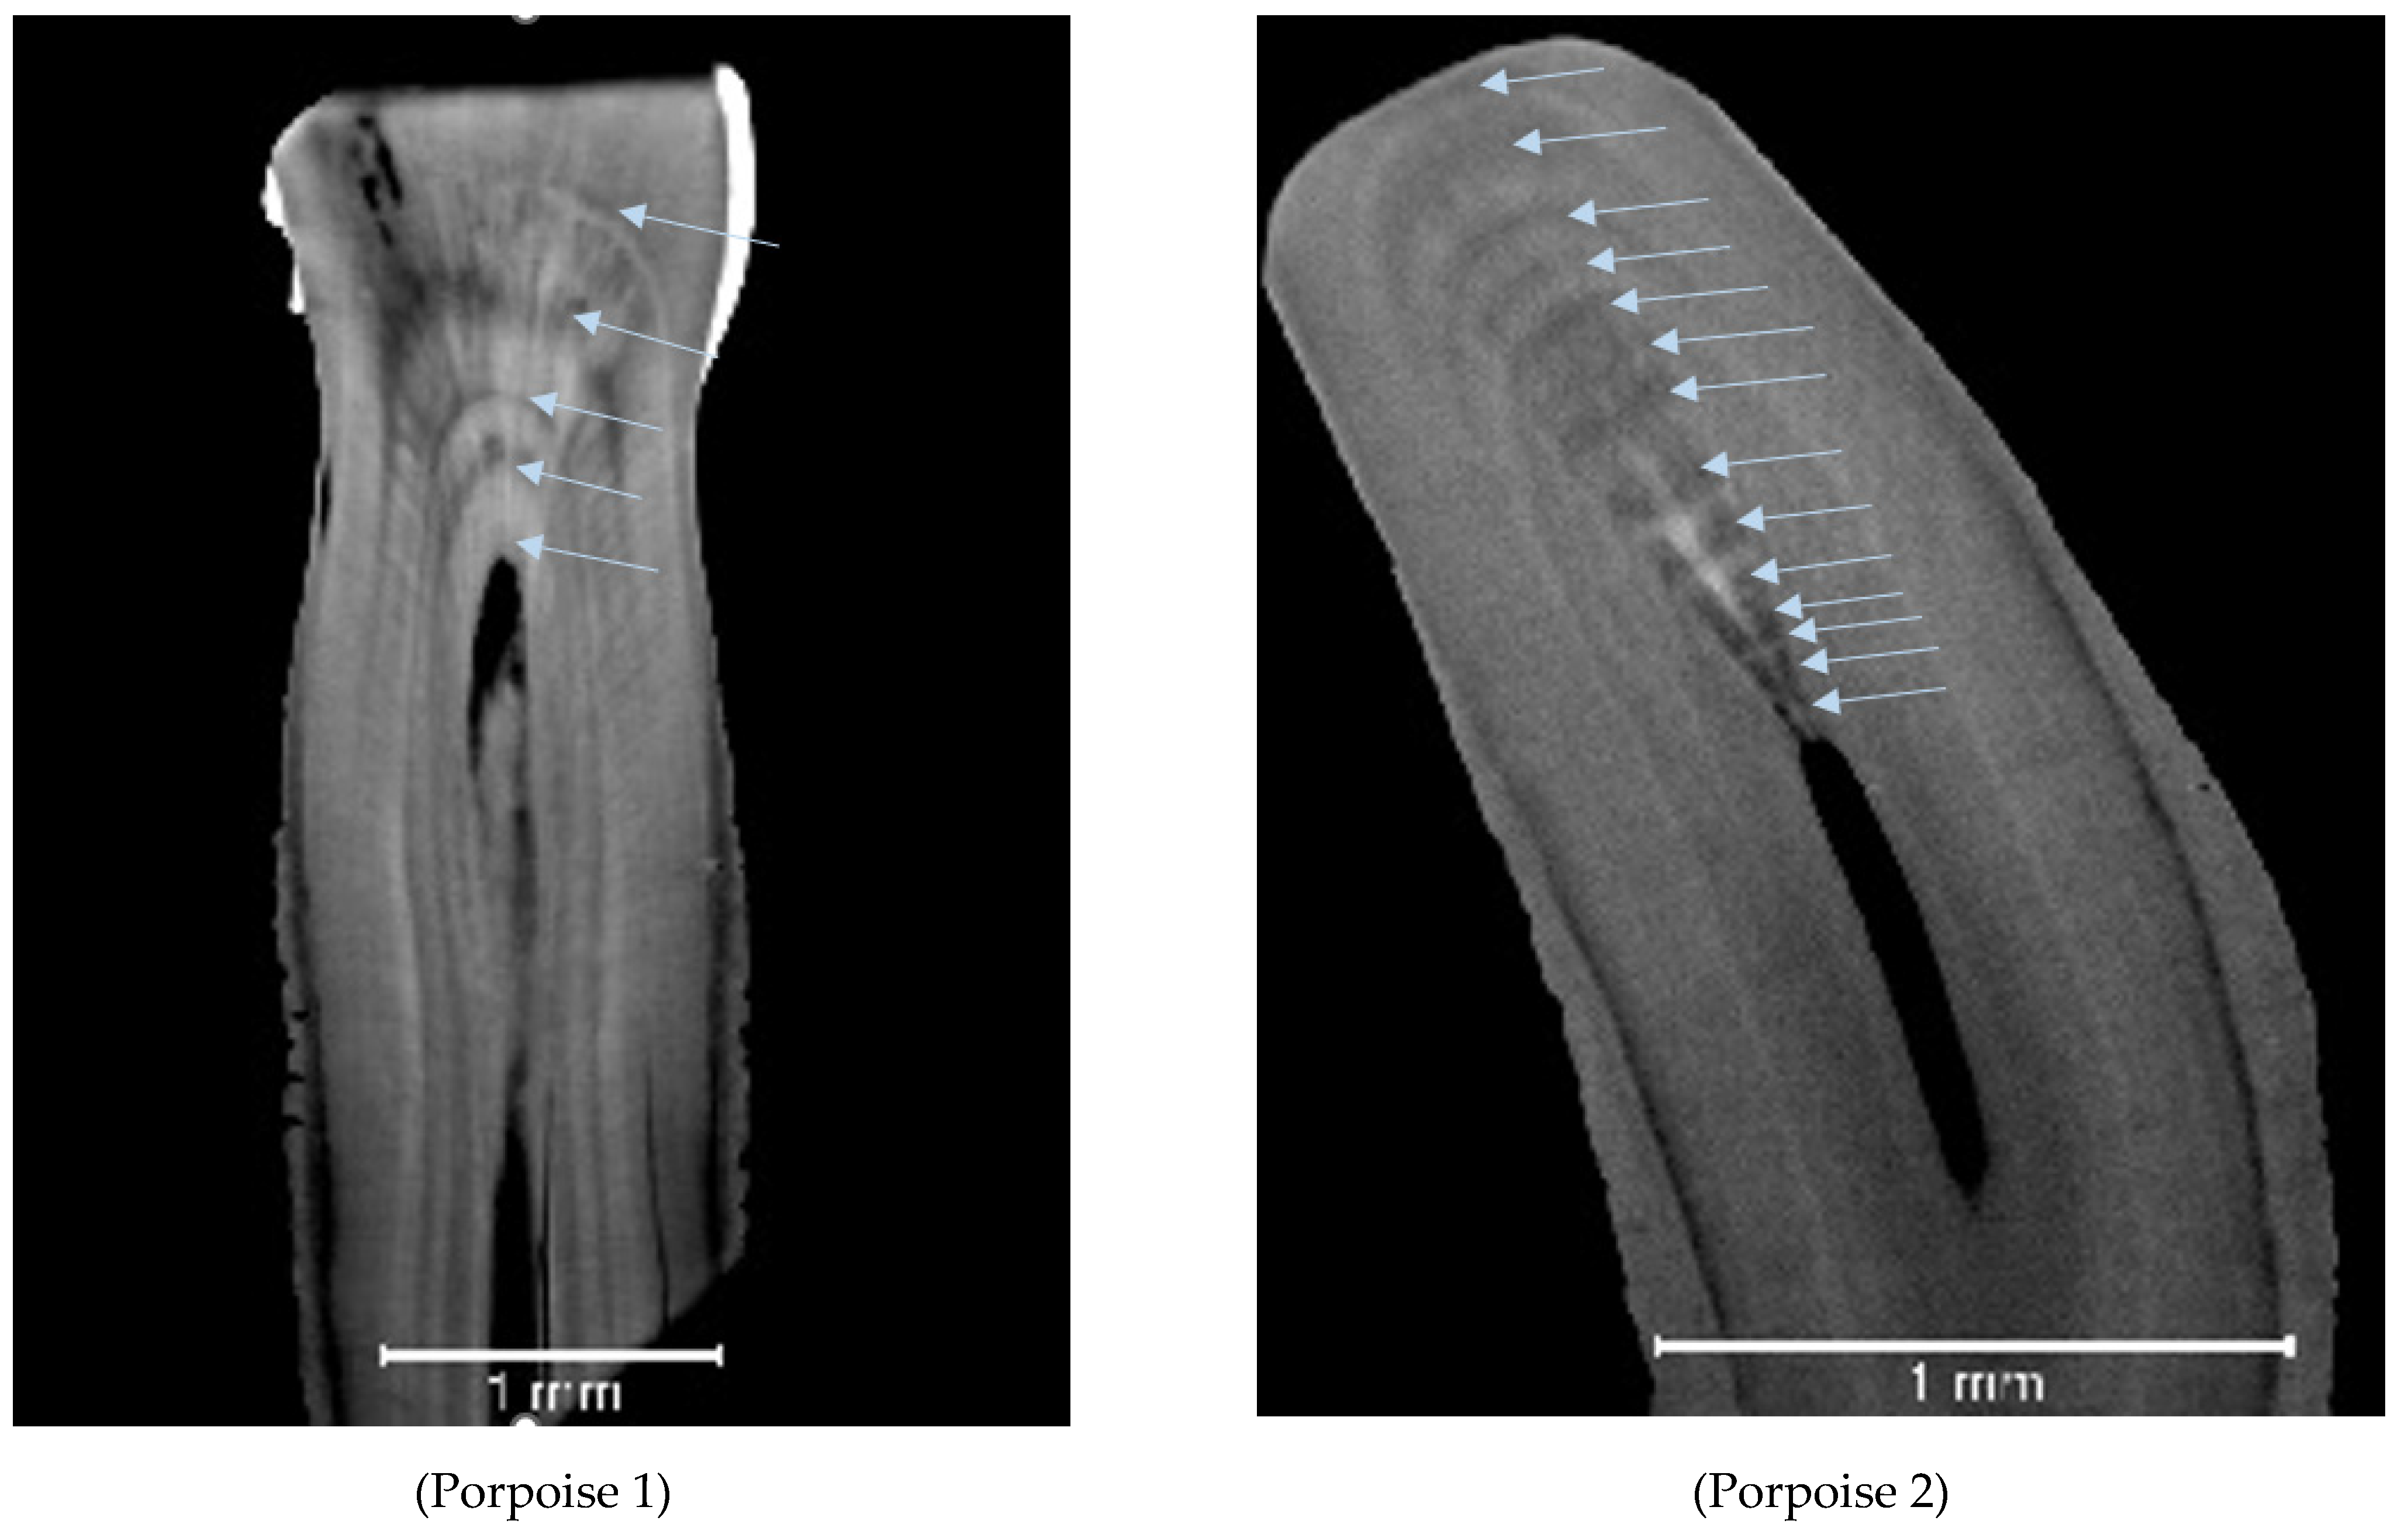

| Harbor porpoise 1 | 5.5 | 5 |

| Harbor porpoise 2 | 13.5 | 14 |